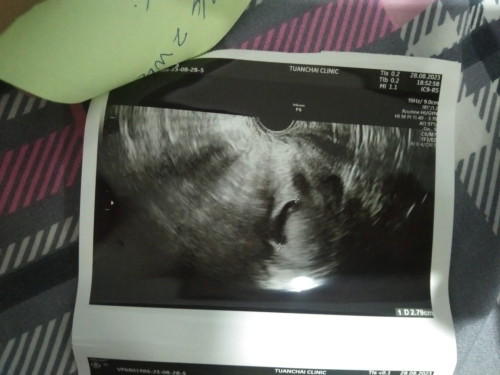

เจอถุงไข่แดง แต่ไม่เจอตัวอ่อน

ปจด.ล่าสุด15 มิ.ย วันนี้ไปซาวด์ผ่านช่องคลอดและหน้าท้องมาเจอแต่ถุงไข่แดง ไม่เจอตัวอ่อน มีแม่ๆคนไหนเจอแบบนี้มั้ยค่ะ แล้วจะเจอตัวอ่อนมั้ย หมอบอกอาจจะท้องลม 2อาทิตย์ให้มาตรวจใหม่ 😢😢